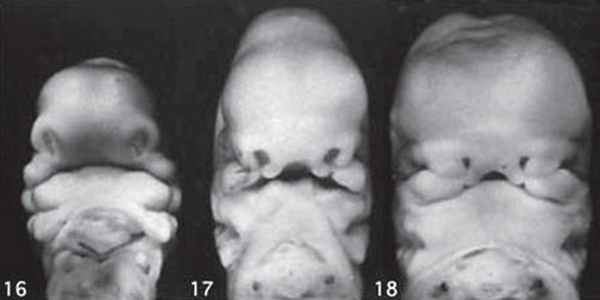

3D/4D объемная визуализация

Использование трехмерного ультразвука, включая визуализацию поверхности, многоплоскостное и многослойное изображение, позволяет точно оценить различные черепно-лицевые структуры и их аномалии, включая расщелину неба (рис. 15, 16) и краниосиностоз. Изображения могут быть полезны для консультирования (рис. 17, 18). Использование 3D (рис. 19) может помочь дифференцировать закрытые и открытые швы. Использование 4D может быть использовано для оценки выражений лица.

Рисунок 17: Плод второго триместра с односторонней расщелиной губы.

3D поверхностное изображение лица плода показывает расщелину (стрелка) на верхней губе (L).

Рисунок 18: Плод второго триместра с расщелиной средней линии.

3D поверхностное изображение лица плода показывает расщелину (стрелка) по средней линии верхней губы (L).